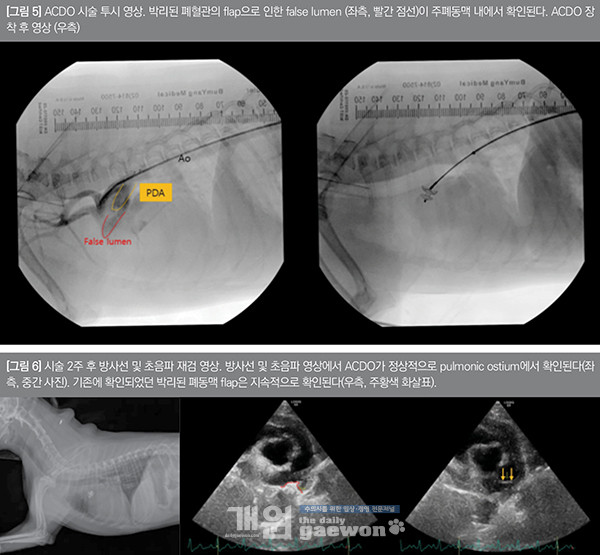

전신 마취 후에 우측 대퇴부를 절개하여 대퇴동맥을 통해 vascular sheath를 장착하고, 이를 통해diagnostic angiographic catheter를 대동맥궁으로 접근시켜 혈관 조영술을 실시하였다. 혈관 조영술을 통해 PDA 형태 및 폐동맥 박리로 인한 flap을 확인하였으며, 초음파 영상과 동일하게 혈관 조영 영상에서도 박리된 폐동맥으로 인해 폐동맥 내 주머니(false lumen)가 확인되었다.

대동맥궁에서 PDA를 통해 폐동맥으로 유입된 조영제는 false lumen 내에 국한된 상태로 폐동맥 원위부의 작은 공간으로 조영제가 폐동맥으로 이동하는게 확인되었다. False lumen에 대한 해부학적 평가를 한 후 4 mm 크기의 ACDO 장착을 하였다.

본 환자는 폐동맥 flap으로 인한 false lumen 내에서 distal disc를 펼친 뒤 ductus 내에서 proximal disc를 펼쳐 무사히 ACDO를 장착하였다. 심장 초음파 및 ductal angiography를 통한 ACDO 장착 여부를 확인한 뒤 wire를 탈착시켜 시술은 종료하였다[그림 5].

환자는 무사히 마취에서 회복하였으며, 시술 당일 퇴원하였다. 시술 2주 후 재검 시 PDA는 ACDO를 통해 정상적으로 폐쇄되어 있었으며, 와류는 소실되었다. 그러나 여전히 박리된 폐혈관의 flap은 확인되었으며, 시술 전보다 false lumen은 매우 작게 확인되었다. LVIDDN 및 LA:Ao ratio 값은 모두 정상 범위로 확인되었다[그림 6].